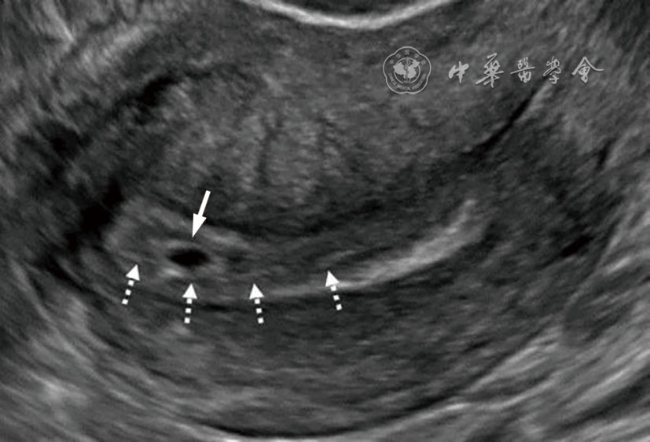

2.输卵管间质部异位妊娠:输卵管间质部异位妊娠较罕见,指受精卵着床于输卵管间质部(嵌入子宫肌壁内的输卵管近端部分)(图4)。超声诊断要点包括:(1)子宫与妊娠囊间滑动征阴性;(2)三维冠状切面重建图像显示子宫肌层部分包绕妊娠囊(妊娠囊周边子宫肌层组织呈“爪形征”),或子宫内膜与妊娠囊间可见薄层肌层组织;(3)间质线征仅偶见(图5),但该征象诊断输卵管间质部异位妊娠特异度较高。应避免使用‘宫角妊娠’或‘宫角异位妊娠’。

图4 输卵管间质部异位妊娠超声图像。图a为经阴道超声横切面灰阶图像,图b为三维超声冠状面重建图像。29岁孕妇(孕5周3天)的妊娠囊(测量游标)与子宫内膜(*)之间存在肌层组织(实线箭头),肌层组织的“爪形征”(虚线箭头)证实妊娠着床于输卵管间质部,提示为输卵管间质部异位妊娠。应避免使用‘宫角妊娠’或‘宫角异位妊娠’。三维超声冠状面重建可更清晰显示妊娠囊与子宫内膜分离,符合输卵管间质部异位妊娠(图4译自参考文献[1])